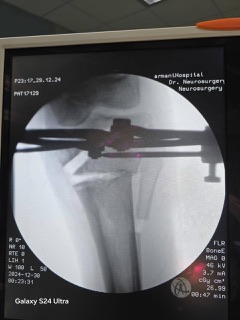

إجراء جراحي متطور باستخدام جهاز إليزاروف

أجرى الأطباء عملية جراحية متقدمة باستخدام جهاز إليزاروف، حيث تم تعديل التقوس في الركبة من خلال شق عظمي دقيق ورفع الجزء الداخلي لمفصل الركبة، مما أسهم في استعادة الطالبة لقدرتها على الحركة بشكل طبيعي، وتخفيف الآلام التي كانت تعاني منها.